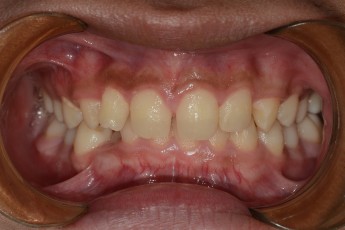

BEFORE & AFTER